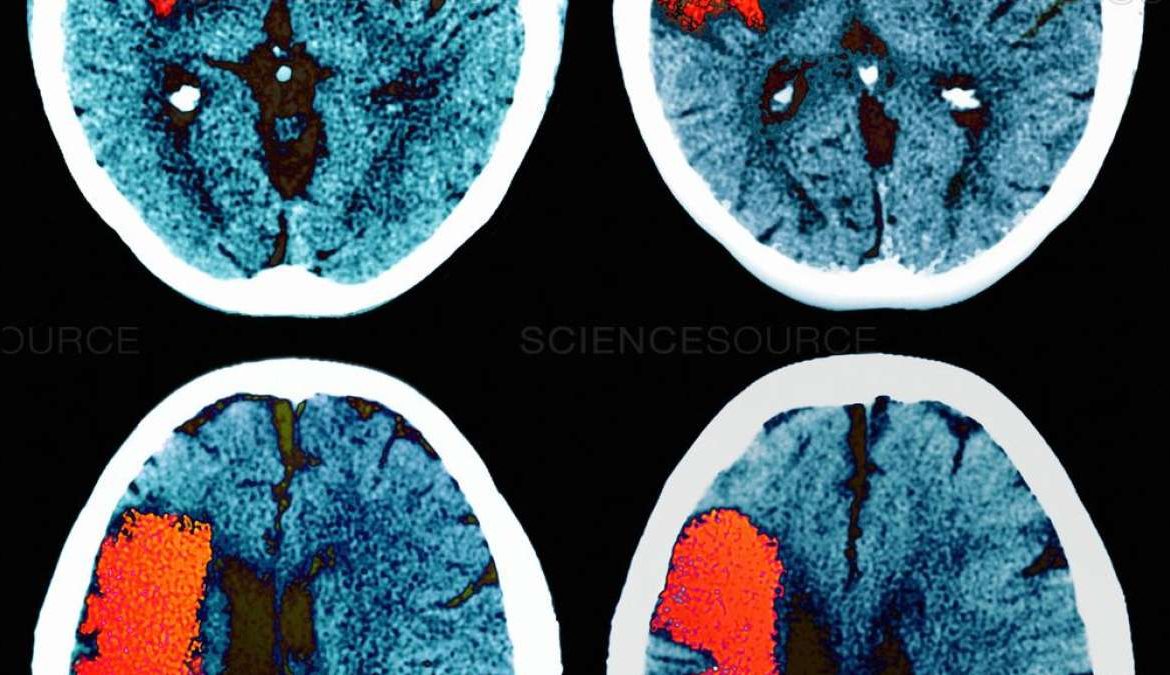

Đột quỵ và mất trí nhớ: chiến đấu với sự mất mát chức năng trong các mạch máu não nhỏ

Một nghiên cứu mới nhận diện các nhân tố phân tử thúc đẩy bệnh ở mạch máu nhỏ – và một loại thuốc có thể giúp phục hồi các chức năng mạch máu bị suy giảm.